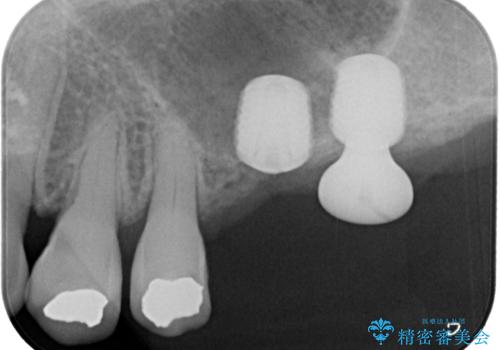

レントゲンから分かるとおり、インプラント埋入に必要な骨の高さが著しく不足している状態でした。

数年前まで当院でも行われていた従来の手法では、骨補填材による上顎洞底の挙上を行い、インプラント埋入に半年以上の期間を必要とするものでした。

しかしながら、ここ数年で流通してきたデンサーバーというドリルと、エキストラワイドショートインプラントの併用により、骨補填材による上顎洞底の挙上なしに埋入が行えるようになりました。

元々の骨量が少なく、通常よりは待機期間が長くなりますが、数ヶ月程度で補綴治療まで行うことができるため、こちらの手法でインプラント補綴治療を行うこととしました。